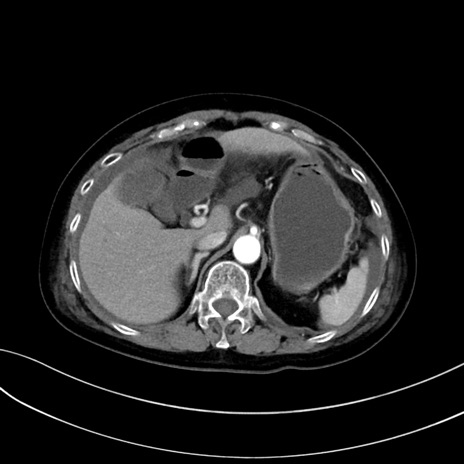

症例13 CT(横断像)1日半後